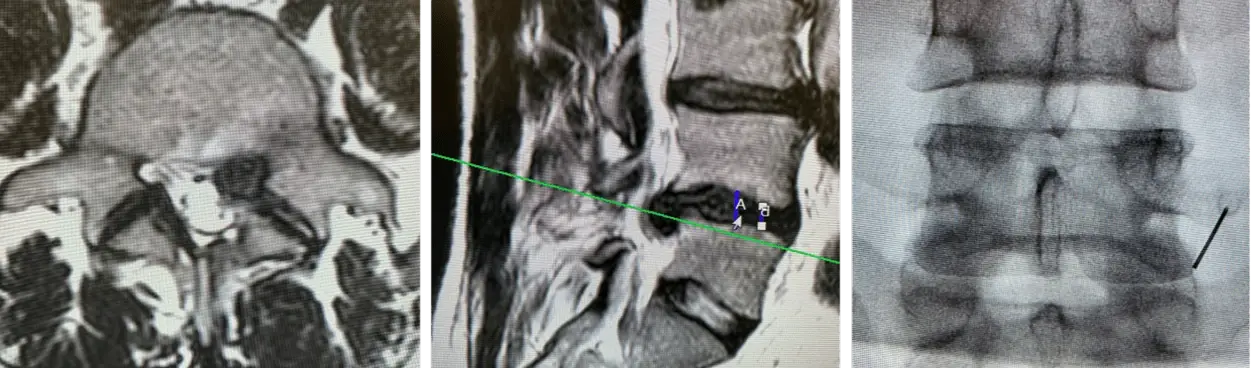

1. L4/5 disc herniation

2. Bilateral foraminal stenosis with retrolisthesis and instability on flexion-extension view

Intra OP radiograhs for the planning of the surgical access.

• L4/5 minimally invasive TLIF - left, to be performed as an outpatient procedure in the ASC.

• Planning to use the Neo Cage System ™ & Neo Pedicle Screw System™ for fusing the segment L4/5